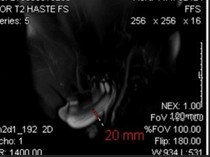

30 Tahun Berlalu, Kisah di Balik Foto MRI Hubungan Seks Pertama di Dunia Terungkap Kamis, 08 Jan 2026 19:16 WIB